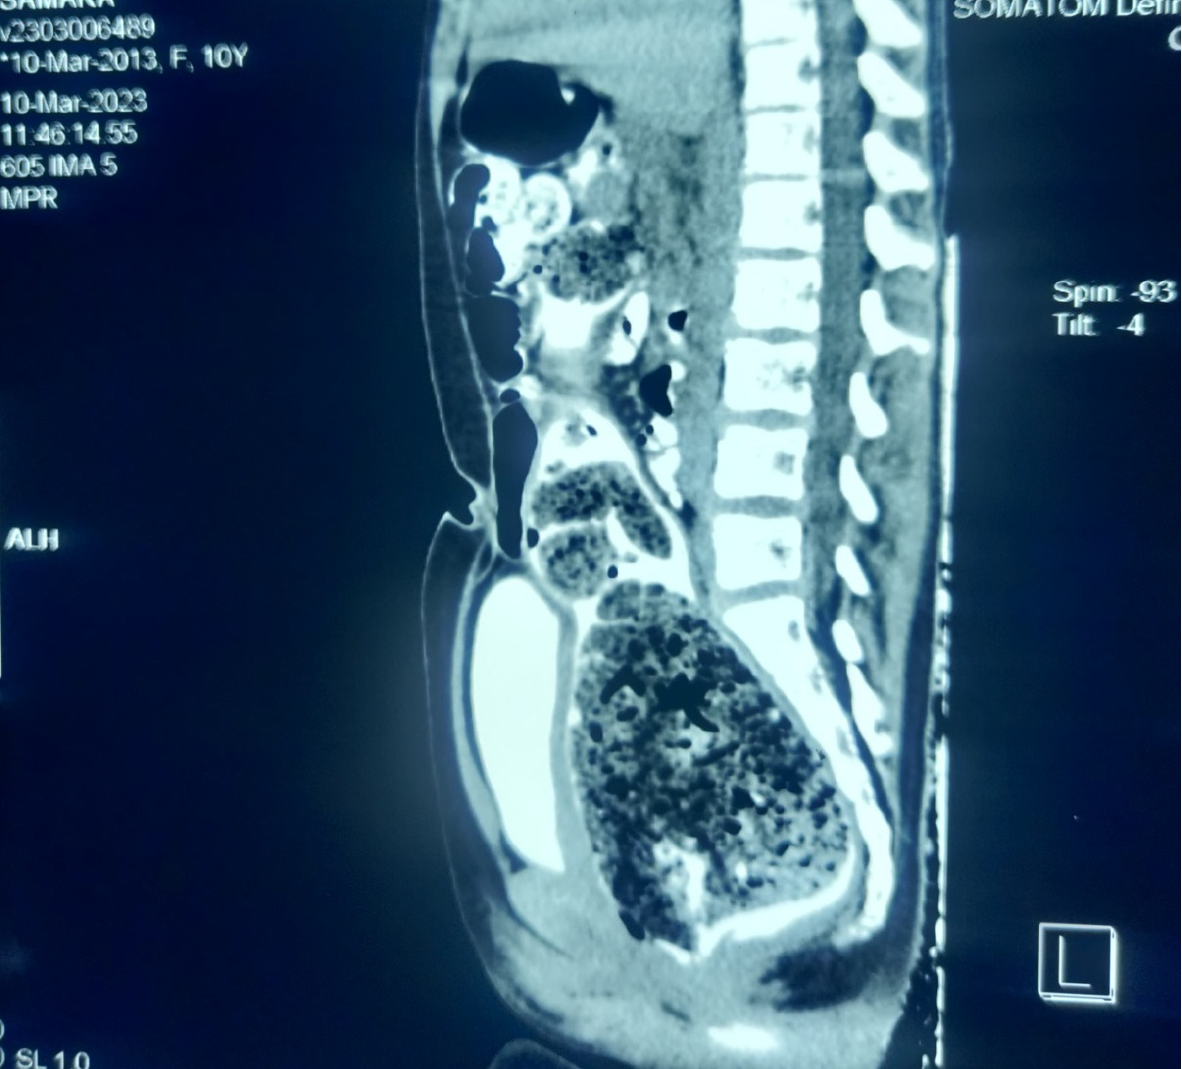

This prospective observational study was done at Department of Pediatrics, Sylhet MAG Osmani Medical College, and Dr. Benzamin’s Pediatric Liver Research Centre and Nutrition Clinic, Mount Adora Hospital, Sylhet, Bangladesh, from January 2022 to December 2024. All consecutive children (< 18 years), diagnosed with OC, were included in our study. OC was diagnosed based on negative history for constipation with fecal impaction on plain X-ray abdomen, which meets Leech criteria for OC (Figure 1). Each abdominal radiograph was divided into three colonic segments and fecal loading was evaluated as per Leech scoring system, where each score between 8 and 15, indicates significant constipation[10]. The sensitivity of Leech score in diagnosis of OC is significantly higher than any other scoring systems[11]. None of them fulfilled the Rome IV criteria for functional constipation and stool type on Bristol Stool Card was from type 3-7 (Bristol stool card was shown to parents/children to mark the stool pattern). The detailed clinical history, physical examination findings, and investigations done before visiting our center were recorded in a predesigned standard data sheet. During history taking, when the complaints of persistent diarrhea, encopresis, anorexia could not be explained by other conditions and needful investigations, then OC was considered. Physical examination of all samples was done by the researcher himself. The following data were obtained during physical examination: (1) Fever; (2) Mouth ulcer; (3) Abnormal thyroid gland; (4) Growth parameters; (5) Skin survey; (6) Per abdominal examination; (7) Tone/reflex of lower limb; (8) Spine of vertebra; (9) Abdominal distension; (10) Height and weight; and (11) Other red flag signs for constipation[12]. Every significant physical finding was recorded. The researcher did meticulous examination to rule out other possible pathologies. If any dilemma was present or not improved satisfactorily, re-examination and re-evaluation was done. Failure to thrive was defined as weight-for-height/length below the < 3rd percentile on the National Center for Health Statistics growth chart. A secondary diagnosis was considered when patients failed to improve after adequate treatment. Weight gain crossing the 3rd percentile of that baby after treatment is considered an improvement. When any red flag sings for constipation were present or patients failed to improve symptomatically, second diagnosis was considered. Investigations like complete blood count (CBC), serum glutamic pyruvic transaminase (SGPT), serum creatinine, urine routine and microscopic examination, culture and sensitivity, ultrasonography of the whole abdomen, Mantoux test, chest X-ray, endoscopy and colonoscopy, computed tomography (CT) abdomen, stool for Xpert MTB/RIF, celiac screening, etc., were done according to patient indications. Children who were diagnosed at presentation with overt constipation, co-morbid disease/chronic disease, on treatment for constipation, and poor drug compliance were excluded from the study. After the diagnosis of OC, treatment was initiated with magnesium hydroxide; for disimpaction 2 mL/kg/day followed by 1 mL/kg/day for 2 months for maintenance therapy and gradual tapering was done over one month. Patients were followed up monthly for 4 months. The treatment end points were improvement of symptoms, reported by caregiver or improvement of physical findings. Ethical clearance was taken from Departmental Review Board, Department of Pediatrics, Sylhet MAG Osmani Medical College Hospital, Sylhet. Informed written consent was taken from every participant's parent and confidentiality of data was strictly maintained.

Figure 1

Figure 1 Fecal impaction at caecum, sigmoid and rectum.